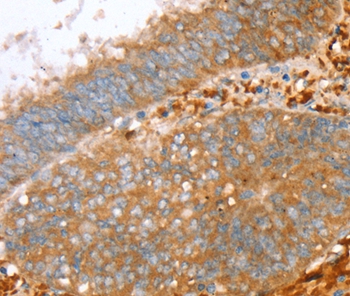

Immunohistochemical analysis of paraffin-embedded Human cervical cancer tissue using #36706 at dilution 1/30.